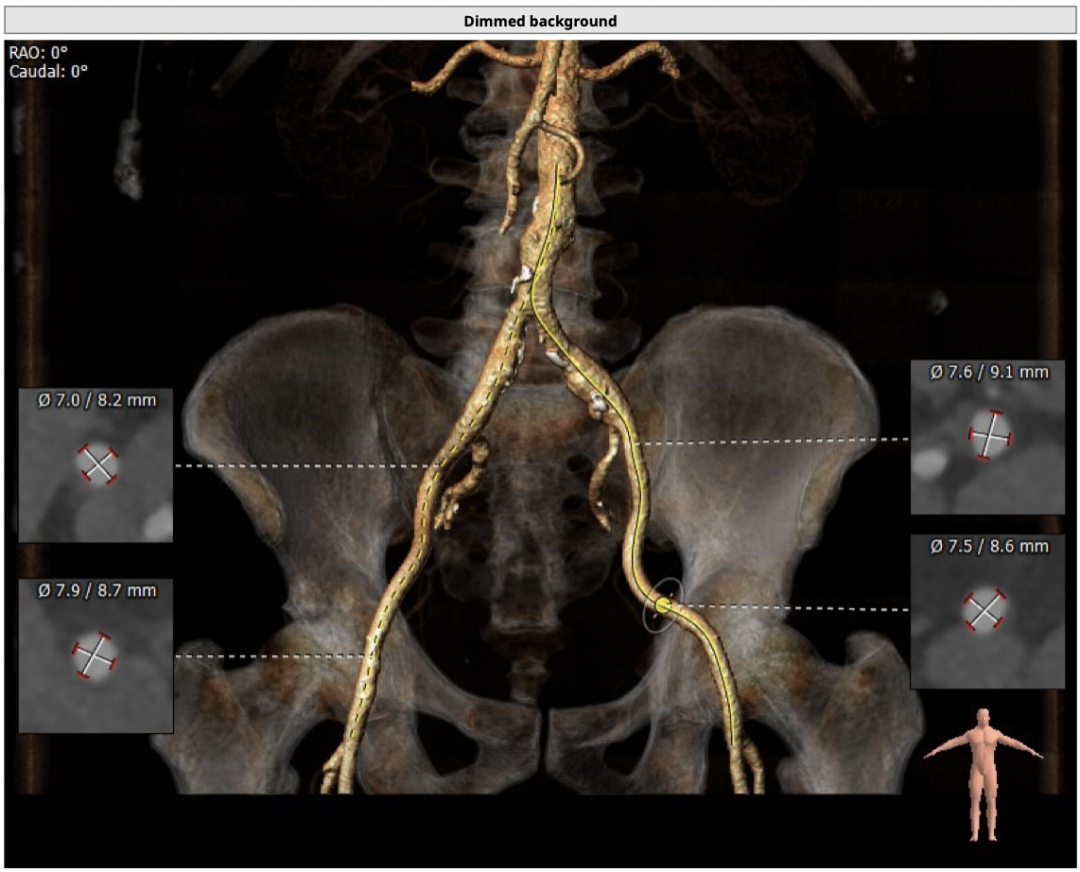

通过FEops报告选型

面积为410.7mm²

周长为73.1mm

周长导出径为23.3mm

面积导出径为22.9mm

平均径为23.4mm

根据瓣环径及瓣上结构,FEops优先推荐L26号,备选L23号